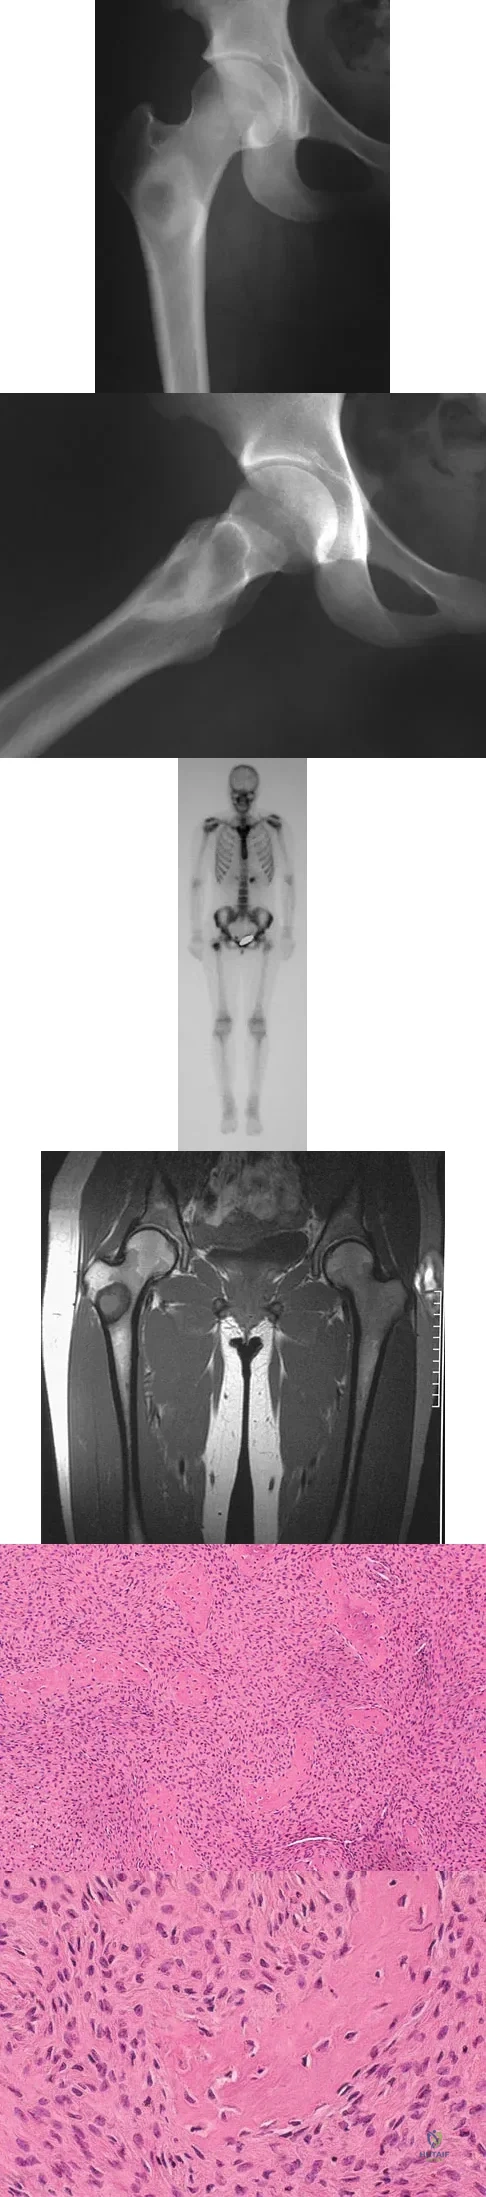

A 16-year-old girl injured her hip in a fall. Radiographs are shown in Figures 14a and 14b. She denies any history of pain prior to the fall and is currently asymptomatic. A bone scan, MRI scan, and biopsy specimens are shown in Figures 14c through 14f. What is the most likely diagnosis?

Explanation:

Although the classic radiographic appearance of fibrous dysplasia is one of a central metaphyseal lesion with ground glass matrix, it is not unusual to see either a more radiodense-appearing lesion or a more peripheral location. The histologic finding of spicules of woven bone without osteoblastic rimming in a bland fibrous background is diagnostic of fibrous dysplasia. The imaging studies could be consistent with low-grade osteosarcoma, osteoblastoma, or osteomyelitis, but all have a very different histologic picture. Observation is indicated in the absence of symptoms, impending fracture, or deformity. Fibrous dysplasia most commonly occurs in the proximal femur. Huvos AG: Bone Tumors: Diagnosis, Treatment, and Prognosis. Philadelphia, PA, WB Saunders, 1991, pp 30-43.